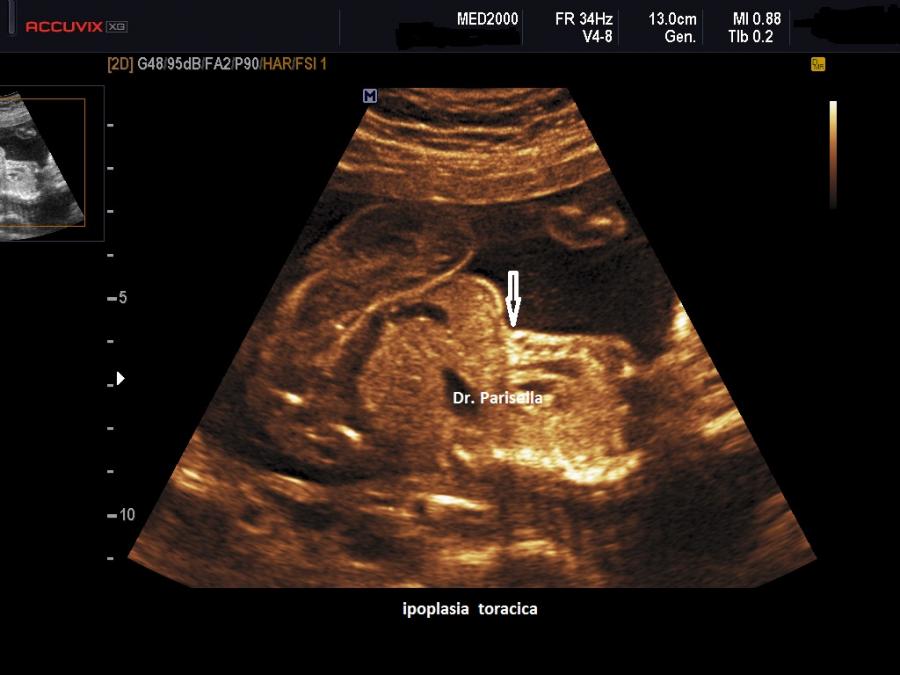

E' una displasia scheletrica caratterizzata da nanismo rizomelico con incurvamento del femore e della tibia. Si associano dismorfismo facciale (con micrognazia e palatoschisi), ipoplasia toracica  con coste corte (di solito sono presenti 11 paia di coste), ambiguità dei genitali fino al sex reversal (cariotipo maschile con fenotipo femminile); frequente è l'ipoplasia della fibula; si evidenzia inoltre piede torto, idrocefalia, macrocefalia.